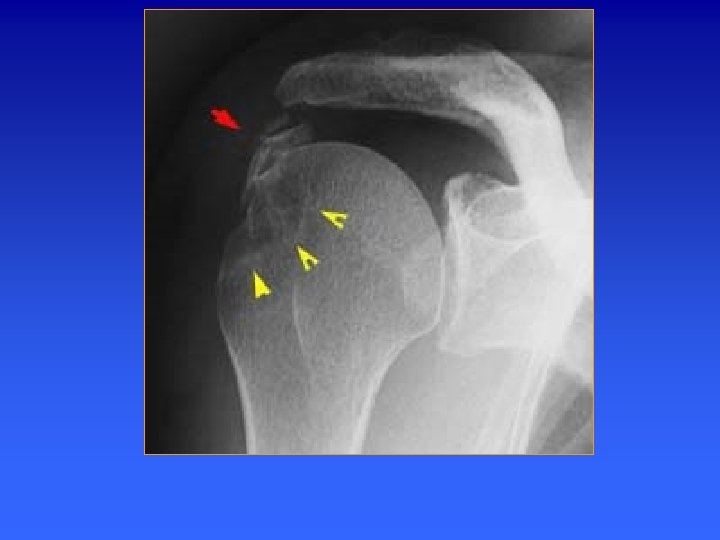

Epaule de face en rotation interne Position du patient Résultat La diaphyse humérale Est coiffée symétriquement par la tête humérale 1 Espace sous-acromial siège de calcification du sous épineux 2 Trochiter, vue de face 3 Berges externe de la gouttière bicipitale A partir de la position RO 4 Trochin saillie en dedans faire une adduction de l’avant-bras, main dans le 5 Horizontalisation du col dos si possible anatomique 6 bord inféro-antérieur de la glène Siège de fracture lors de luxation antérieure de l’épaule

Epaule de face en rotation interne Résultat n Le col anatomique est presque horizontal n la tête humérale coiffe la diaphyse de façon symétrique. n Le trochiter est vu de face n La gouttière bicipitale est interne n Le trochin vu de profil, constitue le bord interne de la métaphyse humérale.